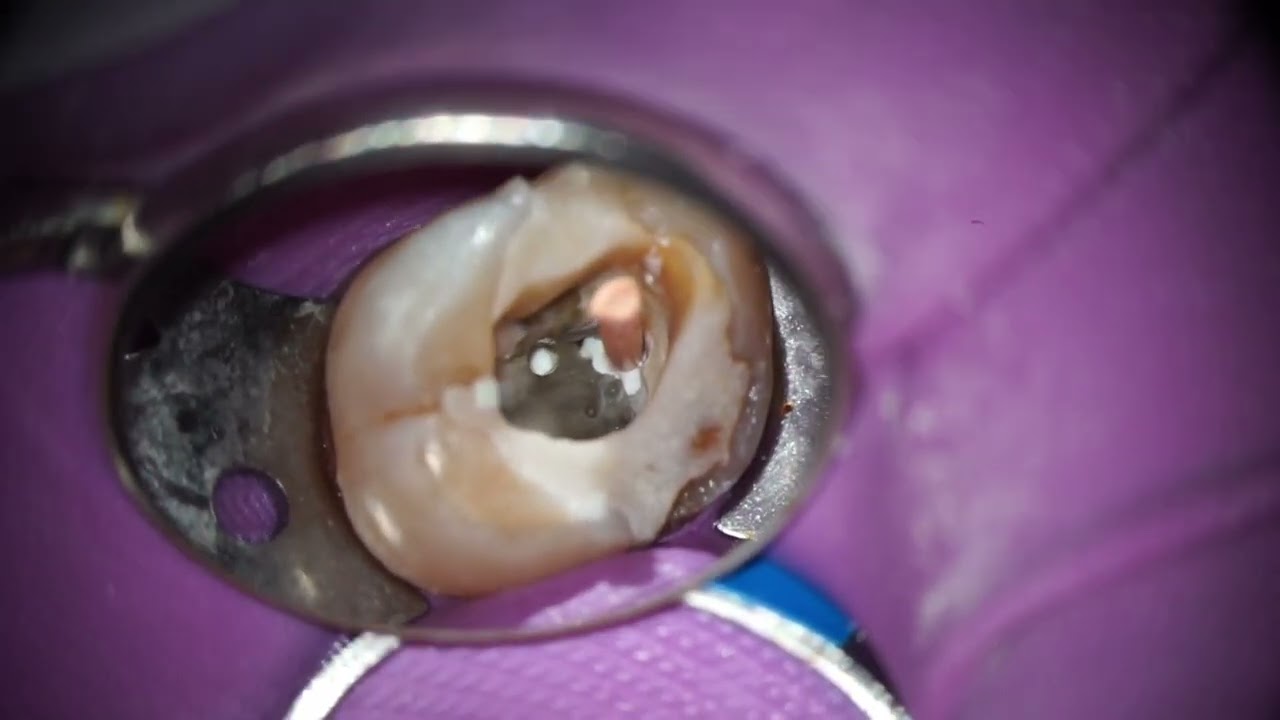

Figure 1 from Case Reports in Maxillary Posterior Teeth by Guided Endodontic Access Semantic Maxillary Endo Access Maxillary left first molar with previous, aborted attempt, to gain endodontic access through existing metallic (amalgam). An access cavity is defined as 'the opening prepared in a tooth to gain entrance to the root canal system for the purpose of cleaning,. This article reviews the basic clinical techniques of performing a maxillary molar endodontic. This study aimed to compare the. Maxillary Endo Access.